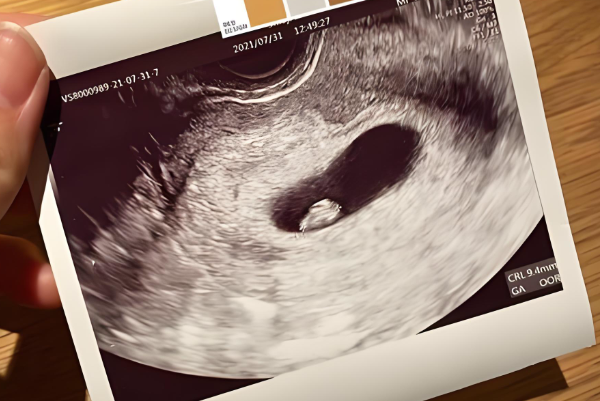

COUTACT US试管怀孕到了11周,做B超检查时没看到胎心这种情况正常与否还需要结合实际孕周来判断,因为试管怀孕的孕周计算有时候会和自然怀孕不太一样,如果孕周算错了,可能胎心还没到该出现的时候,另外,每个人的身体状况不同,胚胎发育速度也会有差异,所以遇到这种情况,先冷静下来,仔细核对一下孕周,看看是不是计算有误,然后再考虑其他因素。

如果孕周计算正确,但11周了还是没见到胎心,这背后其实有好几种可能性,当然,最终还是要通过专业检查来确认,但心里有个底总归是好的。具体如下所示:

1、孕周计算出了岔子:试管怀孕的孕周计算有时候会搞混,比如从移植日算起,或者根据取卵日来推,但如果记错了日期,或者月经周期不规律,就可能把实际孕周算小了。这样一来,胎心可能还没到该出现的时候,自然在B超上看不到。很多人容易忽略这个细节,总觉得日子没错,结果白担心一场;

2、胚胎发育慢了半拍:有些胚胎天生发育就慢点,不像别人家孩子那样按部就班。正常情况下,胎心在6到8周左右出现,但个体差异大,有的可能拖到10周甚至更晚。如果准妈妈身体状态不太好,或者营养没跟上,胚胎可能长得慢吞吞的,胎心自然就晚点露面。这不代表一定有问题,只是需要多点耐心等等;

3、胚胎已经停止发育:这是比较让人难受的可能性,就是胚胎在早期就停止生长了,可能因为染色体异常或者其他内在问题。一旦停育,胎心就不会出现,B超检查也只能看到空囊或者没有活力的迹象。这种情况在试管中不算少见,毕竟辅助生殖技术本身就有一定风险,需要理性面对;

4、检查设备或操作有误差:B超检查不是百分百精准,有时候设备老旧,或者操作人员经验不足,可能没扫到胎心的位置。另外,如果准妈妈肚子脂肪厚,或者憋尿不够,图像不清晰,也容易误判。所以一次检查没看到胎心,别立马灰心,复查一下说不定就有转机。